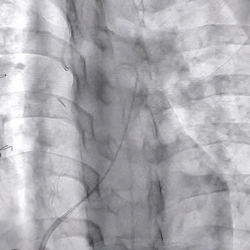

术前造影(可见大量反流) 术后造影(无反流)